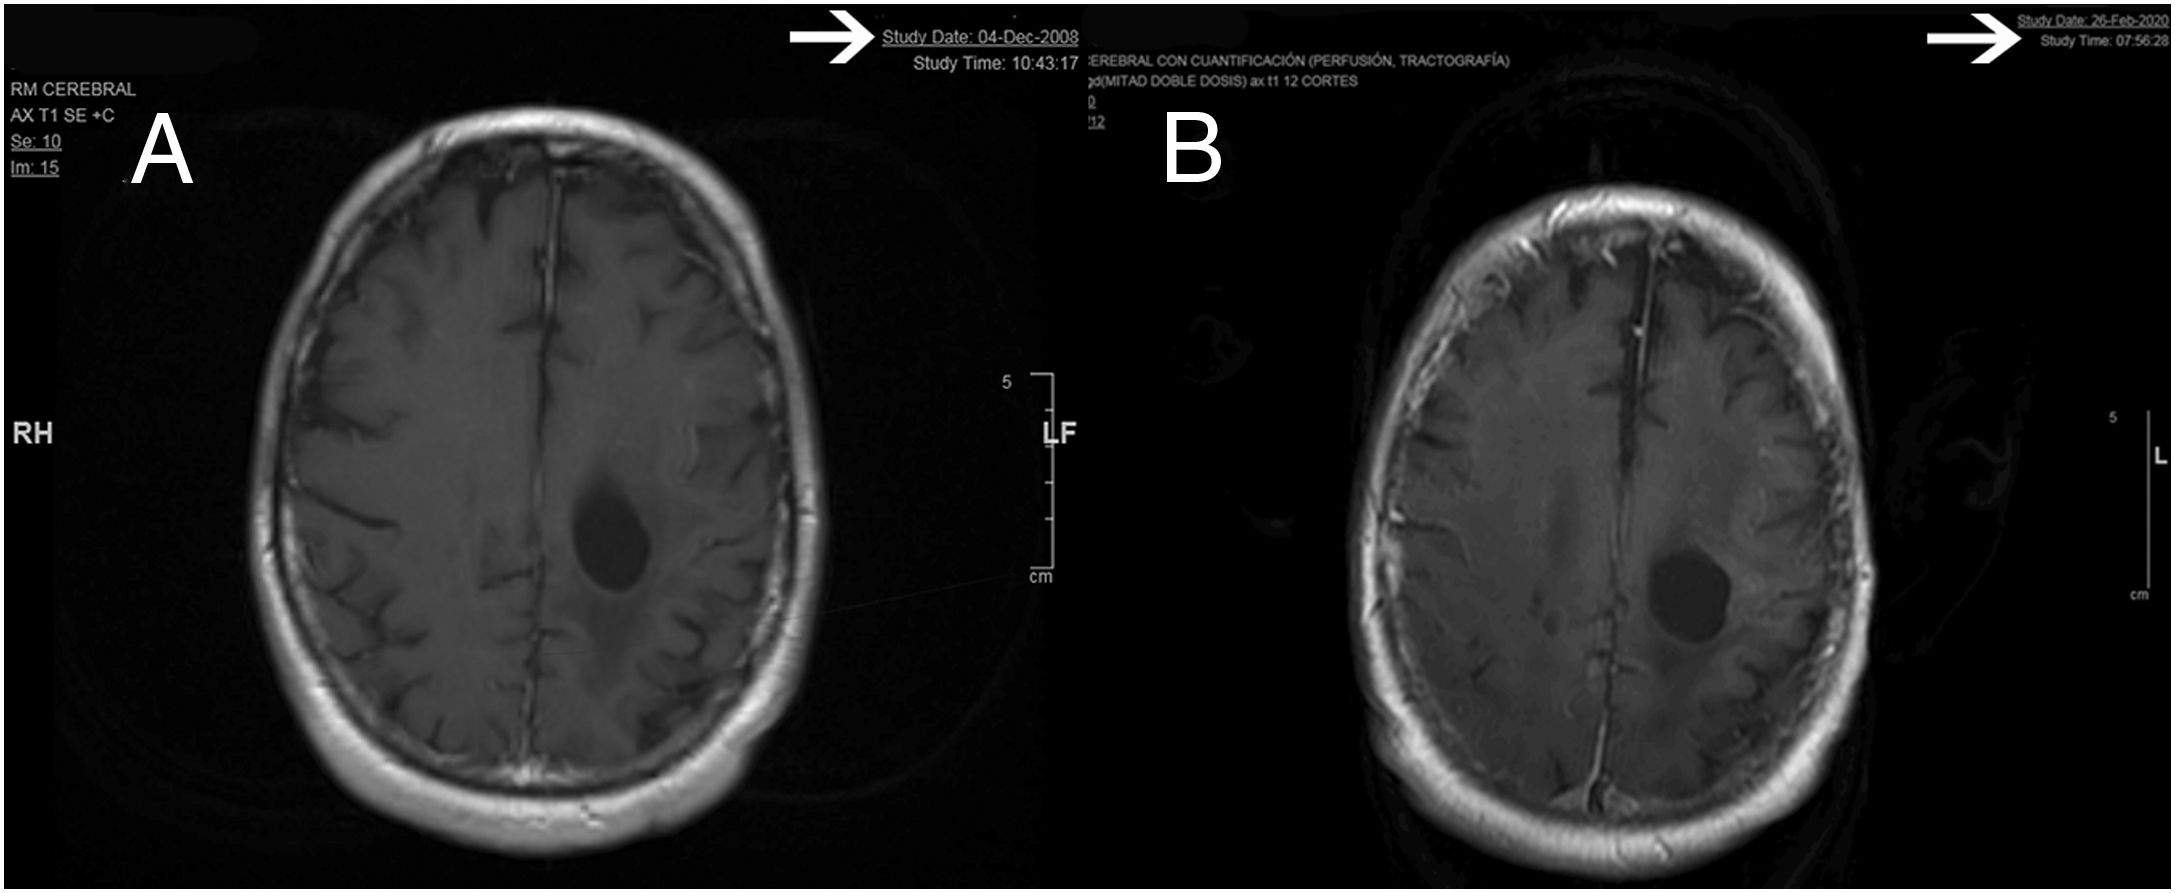

Material and methodWe realize a systematic analysis and identify important factors for long survivor patients. We also show an own case with more of 20 years of survival. We make a new pathological study of the old paraffin block of this patient.

ResultsThe most important variable associated with long-survival between all multivariant studies is the age. When we try to find genetic and molecular alterations in glioblastoma associated with prolongated survival, the MGMT promoter methylation play the most important role. We find a correct diagnosis in the current analysis of our patient’s sample with very long survival.

Material y métodosSe realiza un análisis sistemático de la literatura identificando los factores que pueden influir en los pacientes de larga supervivencia. Se identifica un caso en nuestro medio de más de 20 años de supervivencia realizándose un análisis actual del bloque de parafina que se conservaba del paciente.

ResultadosLa variable que más se asocia a la larga supervivencia en todos los análisis multivariantes es la edad, aunque, cuando se analiza las características genéticas y moleculares de los tumores, parecen existir otras variables como la metilación del promotor MGMT que juegan un papel muy importante. El análisis anatomo-patológico actual de la muestra comprueba la certeza del diagnóstico en nuestro paciente de muy larga supervivencia.